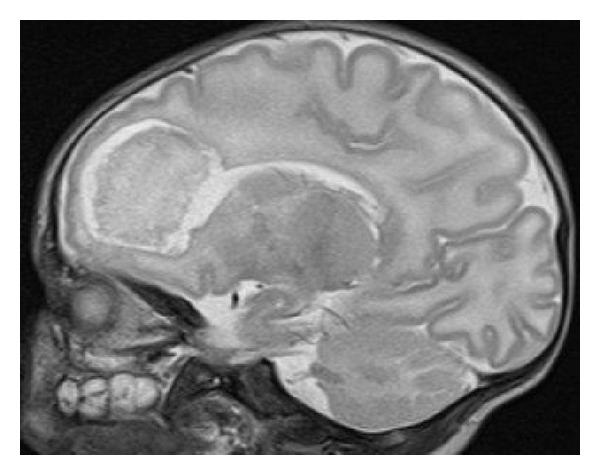

Citrobacter koseri is a rare cause of neonatal meningitis with predisposal for brain abscesses, and therefore responsible for high mortality and serious neurologic sequelae in this age group. We present the evolution and outcome of four cases of C. koseri meningitis. One of them developed brain abscesses and another one died. The cases show the bacteria's propensity for serious brain damage, despite early and adequate treatment, and the high risk of long-term neurologic complications in survivors, which imposes a close follow-up.

科氏柠檬酸杆菌是新生儿脑膜炎的罕见病因,易引发脑脓肿,因此导致该年龄组的高死亡率和严重神经后遗症。我们报告了4例科氏柠檬酸杆菌脑膜炎的病情发展及转归。其中1例发生了脑脓肿,另1例死亡。这些病例显示,尽管进行了早期且充分的治疗,该细菌仍有导致严重脑损伤的倾向,且幸存者有长期神经并发症的高风险,这就需要密切随访。